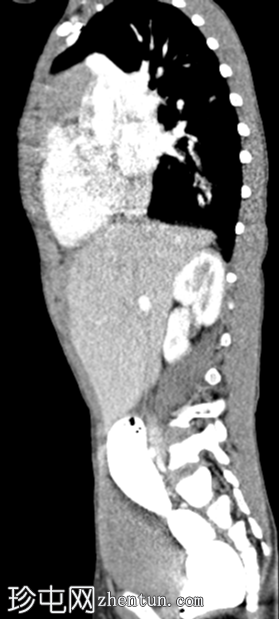

CT

矢状面C+期

动脉期

左侧膈疝通过位于左膈中部的一个缺损形成,伴有纵隔向右侧移位,下方左塌陷。

脾脏、大肠和小肠均有疝气,同时伴有肠系膜上血管疝气。

胃位于下部,靠近主动脉分叉处。